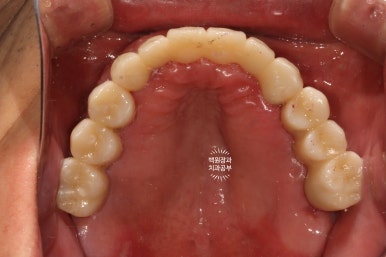

시간이 지나.. 최종 보철물을 만들어드리는 시간입니다.

약 한달간의 씹는 연습을 마치게 되면, 이제 본격적으로 최종 보철물을 제작해드리게 됩니다.

지르코니아 재질로 만들어진 크라운은 심미적으로도 유리하며, 그 단단함은 성인 남성이 넉넉히 사용하여도 깨지지 않을 정도에요.

치아 색이 약간 노랗다 생각하실수도 있으나, 피부색에 맞추어 제작되므로 너무 걱정하진 마세요!

오히려 너무 밝은 하얀 치아가 어색한 분도 많이 있으시기 때문입니다.

이렇게 보면 측면 모습도 상당히 괜찮고....

잘 보시면 치아와 치아 사이에 틈이 있는 것을 보실 수 있으실텐데요, 이 경계는 앞니 보철물/어금니 보철물의 경계로 추후에 보철물의 수리가 용이하기 하기 위함입니다. 더불어 치실을 쓸 수 있게 하는 공간으로 반드시 필요한 포인트!